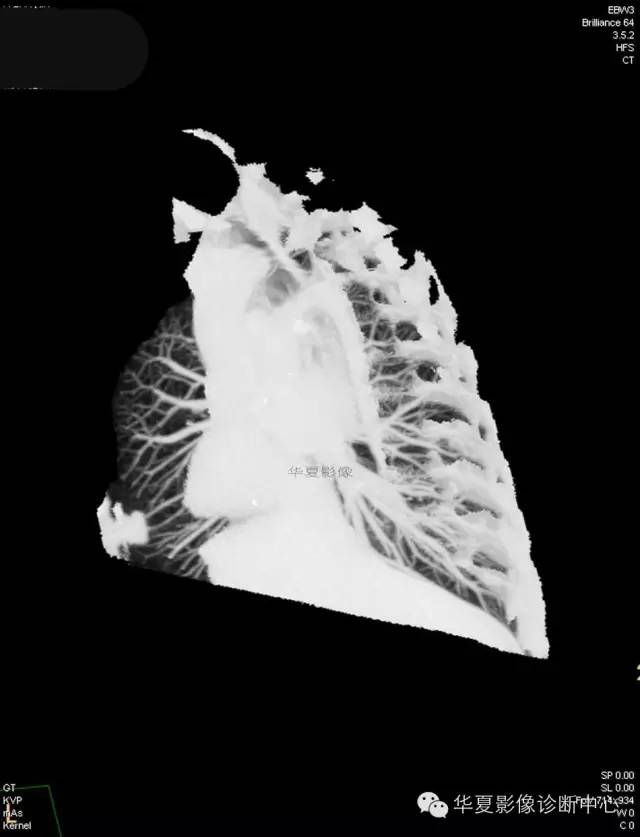

【病例学习】典型周围型肺癌CT病例一例

女,56岁,其父因肺癌去世,自觉胸部疼痛不适来诊要求拍胸片。

1.右肺上叶:肺组织1块,大小13×4×7cm。切面棕红色。2.右肺上叶肿物:灰白色组织一块,大小3×1×1.5cm。切面灰白色。3.右肺中叶结节:灰白色绿豆大组织1块。4.淋巴结:灰黑色绿豆大组织1块。

(右)肺中分化鳞状细胞癌。浸及胸膜。支气管残端切净。淋巴结未见癌转移(0/10)。